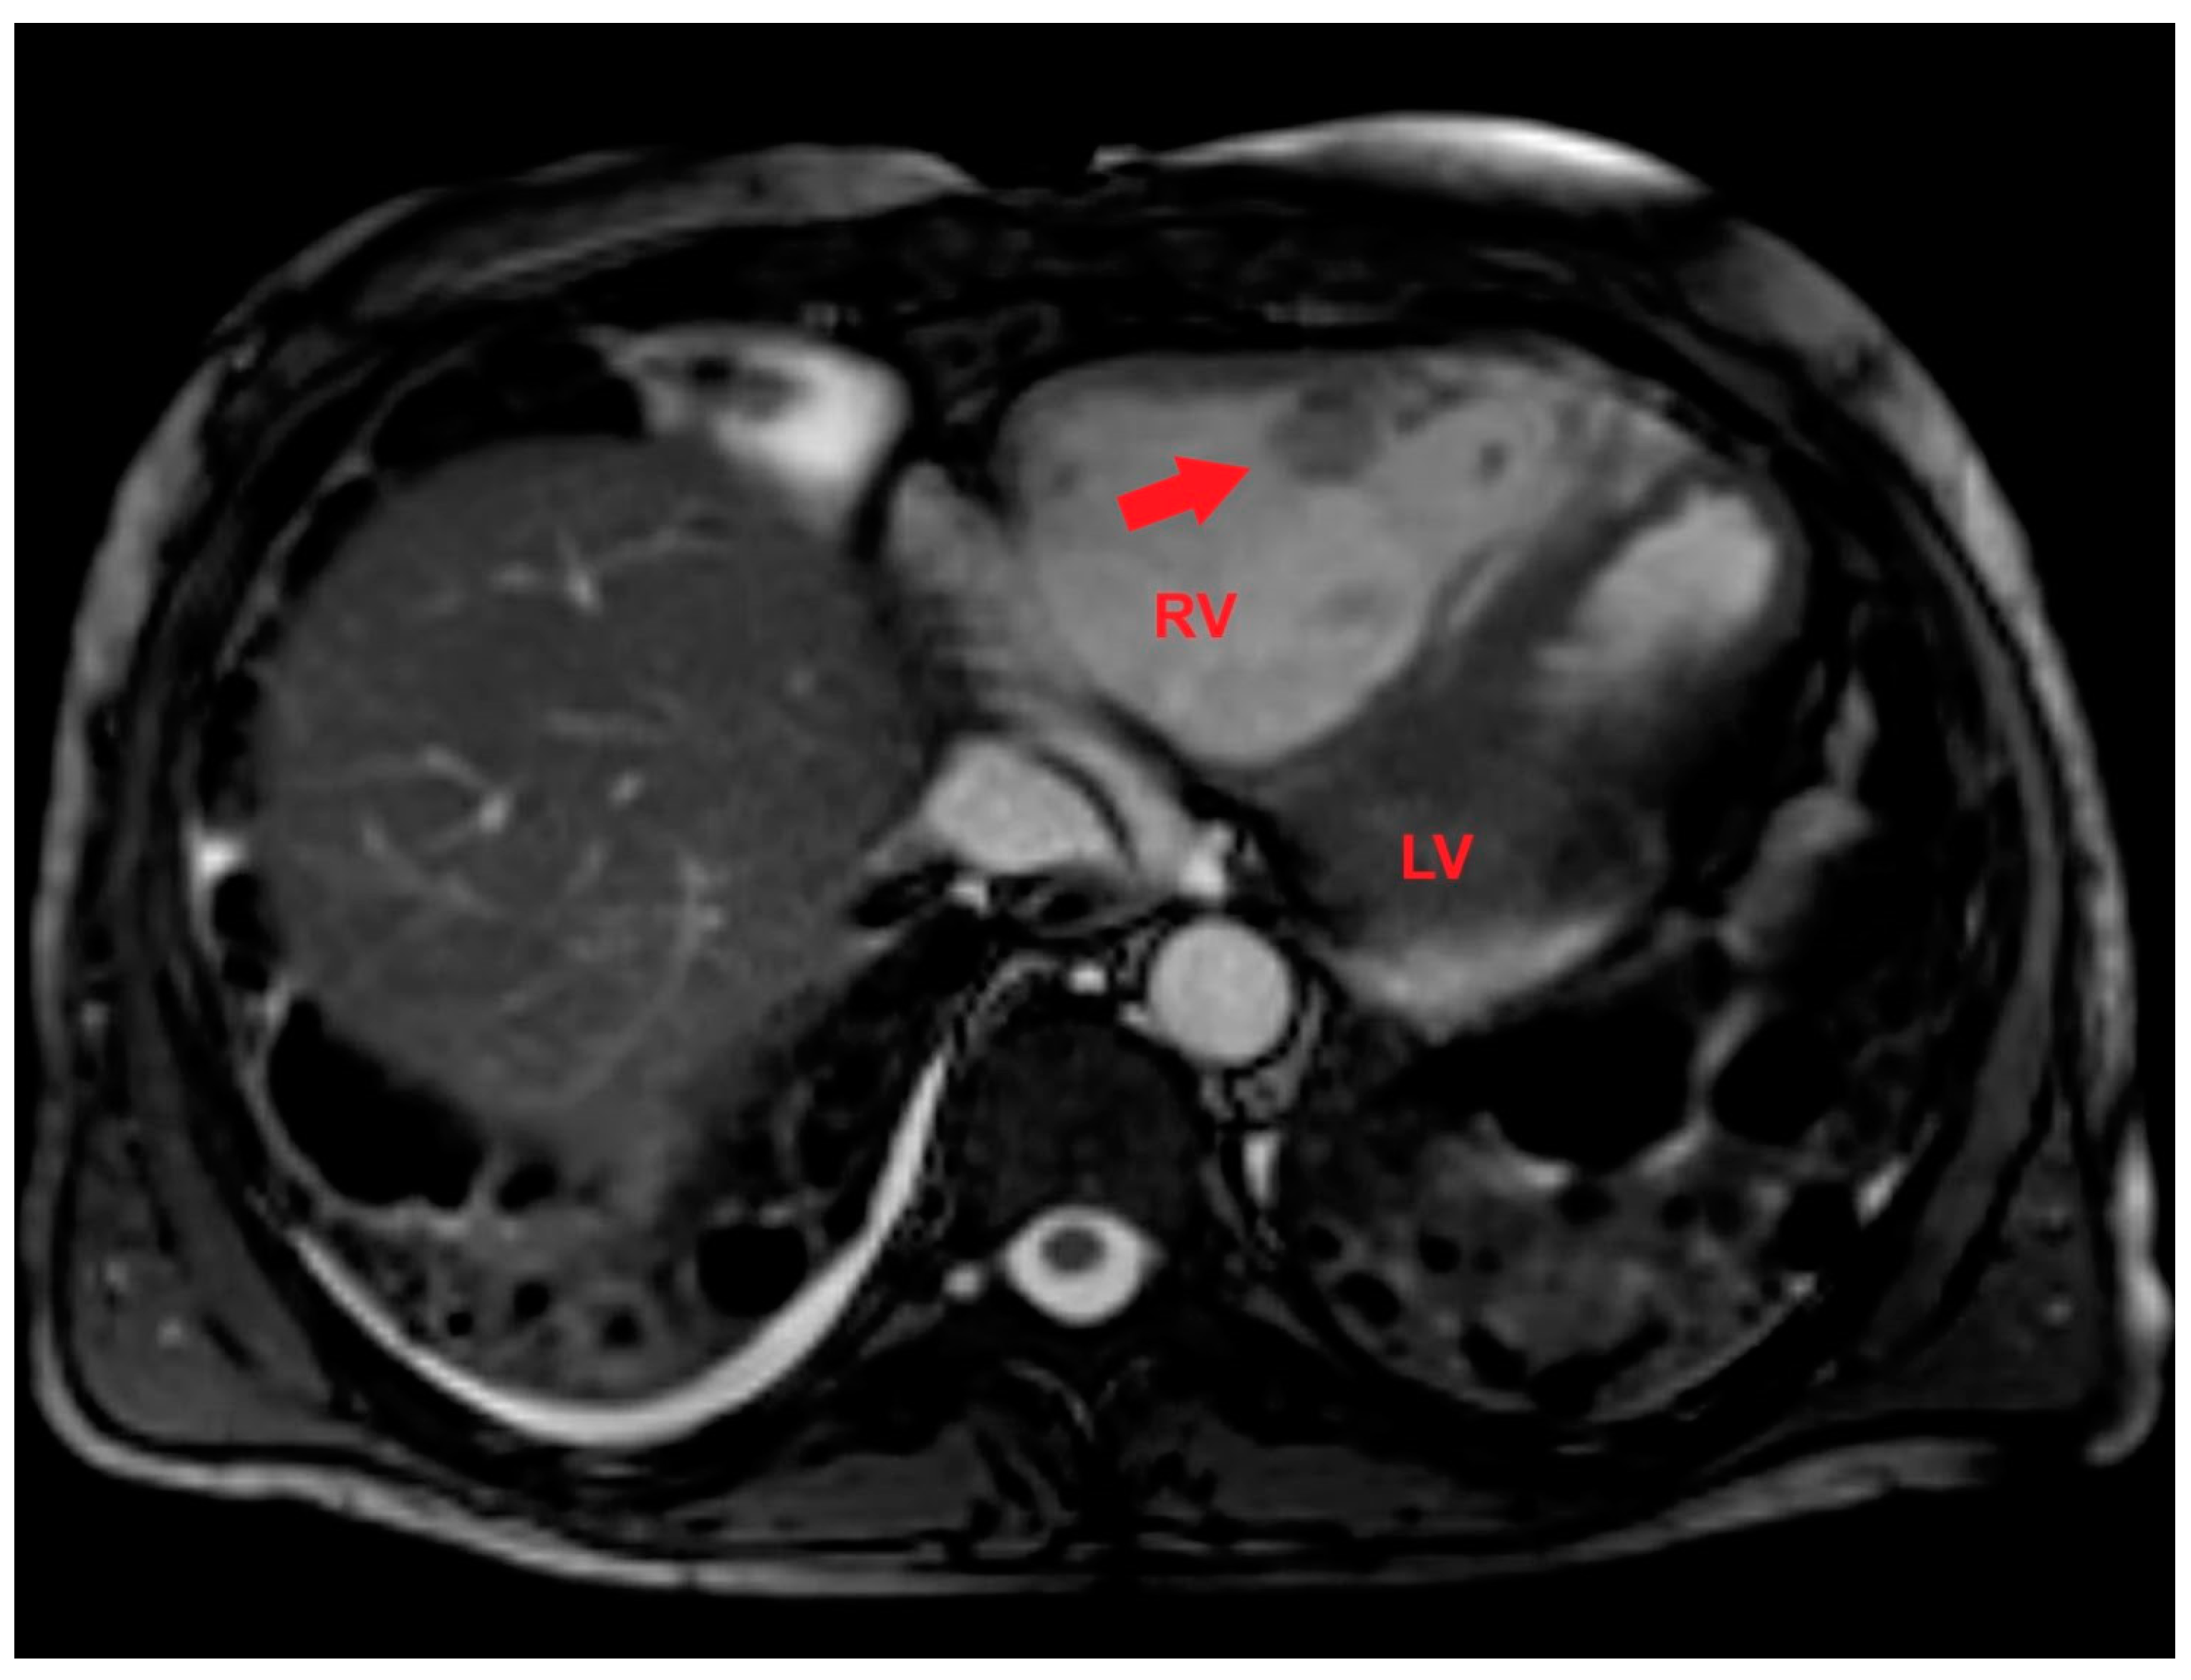

After multidisciplinary discussion, a late gadolinium enhancement (LGE) cardiac magnetic resonance (CMR) was performed. LGE-CMR allowed to detect a RV mass with a central area of colliquative necrosis and inhomogenous peripheral enhancement (Figure 7).

Figure 7. Axial late gadolinium enhancement cardiac magnetic resonance showing a right ventricular mass (red arrow) with a central area of colliquative necrosis and inhomogenous peripheral enhancement. LV, left ventricle; RV, right ventricle.